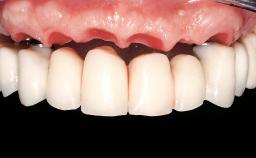

Immediate Loading of Two Implants in the Mandible and Final Restoration with a Bar-Supported RDP

A 56-year-old female patient was referred to the clinic because of retention problems with her mandibular denture. She had been completely edentulous for more than 33 years and wore her sixth set of complete conventional dentures, which had been delivered 5 years previously. An oral surgeon had performed a vestibuloplasty in the interforaminal region of the mandible with a piece of skin tissue 12 years earlier. The panoramic radiograph and lateral cephalometric radiograph exhibited the hypotrophy of the inferior alveolar process. The mandible was a Cawood class VI,and the height of the mandible in the interforaminal zone was 15 mm.